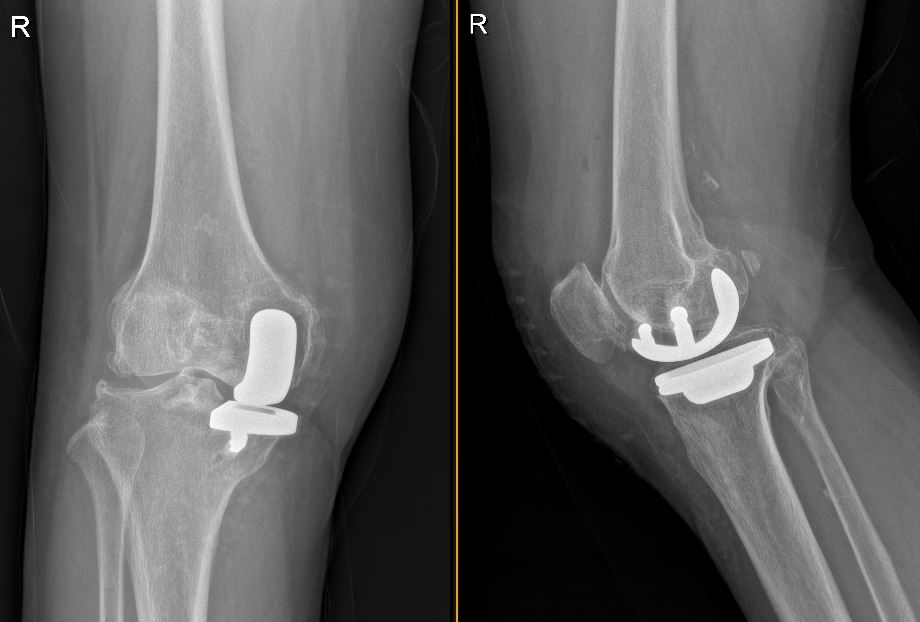

单髁置换 : “只修坏的那一块,能留的尽量都保留”

2. 只换“坏半边”,保留好组织 :换掉磨损严重的那一侧关节面,保留大部分正常骨头、软骨和韧带,膝盖的“原装结构”保留得更多,运动感觉更接近自己的膝盖。

4. 持续监测和评估:定期进行X光等影像学检查,监测假体的位置和稳定性,评估关节功能恢复情况。